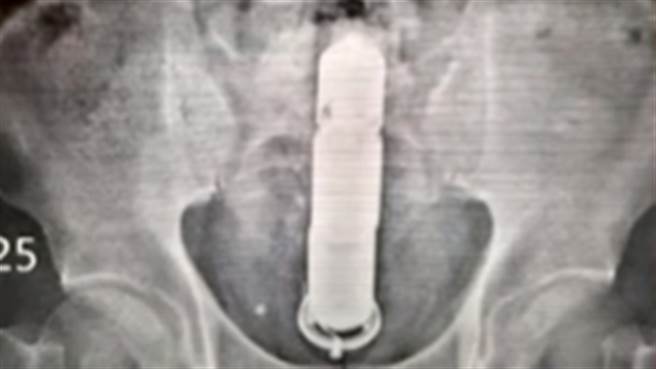

陈荣坚于谈话性节目《医师好辣》中分享,某日凌晨1时许,他在医院休息室突接到急诊护理师通报,一名50多岁男子因肠道有异物到医院急诊室就医,紧急照X光发现一根近30公分长的棒状物卡在肠道中,但无论医师怎么询问男子及男子太太,两人都支支吾吾,说不出个所以然。

直到陈荣坚说恐要开刀处理时,男子才透露,因在家防疫无聊,与太太会研究各种不同的闺房情趣,没想到太太将电动按摩棒塞入他的肛门中,一个不小心推得太深,以致于拔不出来。

陈荣坚说明,由于现在是新冠疫情流行期,若要进开刀房手术,患者必须先进行PCR检测,才能麻醉,因此一度尝试在简易手术室替男子拔出,但「摸得到拿不到」,最后还是只有开刀一途。

陈荣坚说,手术用腹腔镜进入肚子,再打2个小洞,结果发现电动按摩棒的电力还很充足,仍在肠道中不停震动,导致男子不断地喊「肚子痛」,在开刀团队合力协助下,终于将其取出。陈荣坚忍不住提醒,疫情下纾压的方式有很多种,「但东西不要乱塞」。